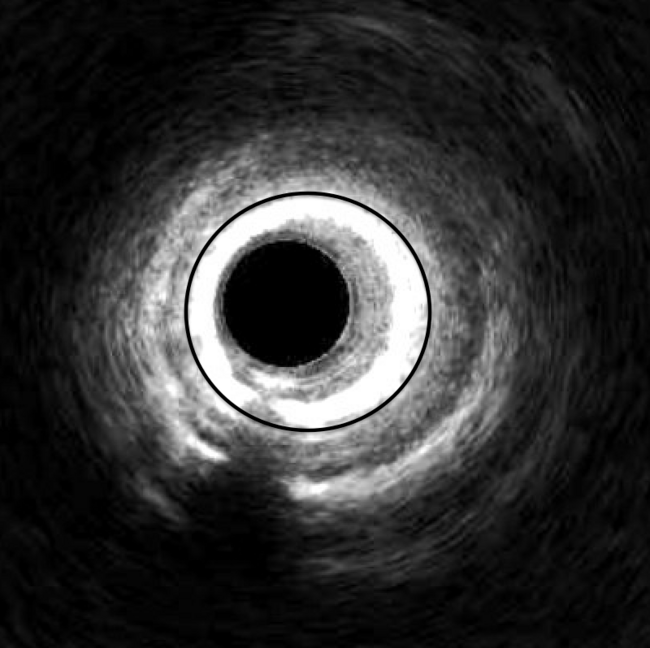

Figure 1. Intravascular ultrasound (IVUS) imaging of a left anterior descending artery showing in-stent restenosis (black circle).

Video 1. Intravascular ultrasound (IVUS) of a left anterior descending artery with in-stent restenosis.